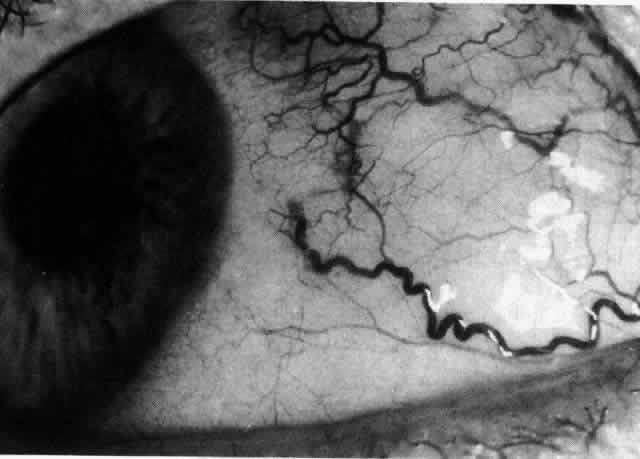

The characteristic features of necrotizing scleritis on fluorescein angiography are hypoperfusion and, eventually, nonperfusion of the vascular networks (Figs. 40 through 43).26 The initial changes are on the venous side of the capillary network; the transit time of the dye increases even if the eye is red and congested. If the disease process persists or has been present for a long time, thrombosis and permanent vaso-occlusive changes occur. These vessels (or the occluded capillary network) are bypassed by the opening of anastomotic channels. New vessels in a granuloma give rise to deep intrascleral leakage of dye (see Fig. 43). Conjunctival and episcleral involvement by the destructive change is late but is always preceded by vaso-occlusive changes that can sometimes be detected with use of the red-free light on the slit lamp (Figs. 44 and 45).

Fig. 40. Early necrotizing scleritis. There is characteristic yellow discoloration of the sclera underlying the conjunctiva at a point of necrosis. In this instance a small filament of tissue has penetrated the conjunctiva.

Fig. 41. Late stage of fluorescein angiogram adjacent to the site of necrosis in the same patient as in Figure 40. Although the eye is uniformly congested, the area near the necrosis shows vascular shutdown, whereas the rest of the conjunctiva and episclera is normally perfused.

Fig. 42. Late arterial phase of fluorescein angiogram in a patient with necrotizing scleritis. All the vessels except the main trunk and the vessels around the limbal perforating vessels are occluded and remain unperfused throughout the angiogram.

Fig. 43. Late venous phase of angiogram of a patient with necrotizing scleritis showing late deep leakage from vessels on the surface of the sclera and leakage of the capillary network at the limbus and the vessels draining it, together with poor or absent perfusion of the remaining vessels.

Fig. 44. Necrotizing scleritis. An avascular patch is seen in red-free light. If left untreated, this will progress to the situation found in Figure 45.

Fig. 45. Necrotizing scleritis. An area of necrosis is evident in the eye of this patient with localized Wegener's granulomatosis. The conjunctiva adjacent to the white necrotic tissue becomes adherent to the underlying episclera.